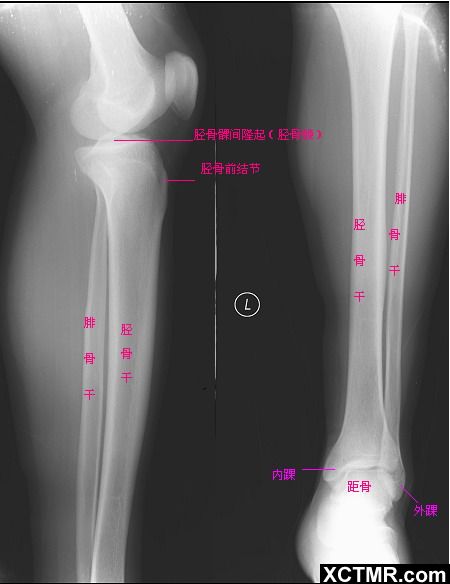

图1  胫腓骨X线正侧位X线像

小腿骨的X线解剖  常规摄前后位及侧位X线片。正位片上胫、腓骨并行,长度相同,上、下端部分重叠,于骨干部分开。胫骨内外侧髁下方能见到致密骺线,正常胫骨粗隆是内、外侧髁在前面下部相连形成的骨性隆起,以侧位X线片观察最清楚。胫骨干中部较细,骨密质厚,前缘达l0mm,后缘约5mm。胫骨下端膨大,内侧下端可见内踝。腓骨于侧位片上清楚显示较胫骨偏后,下端膨大形成外踝,位置较内踝低。